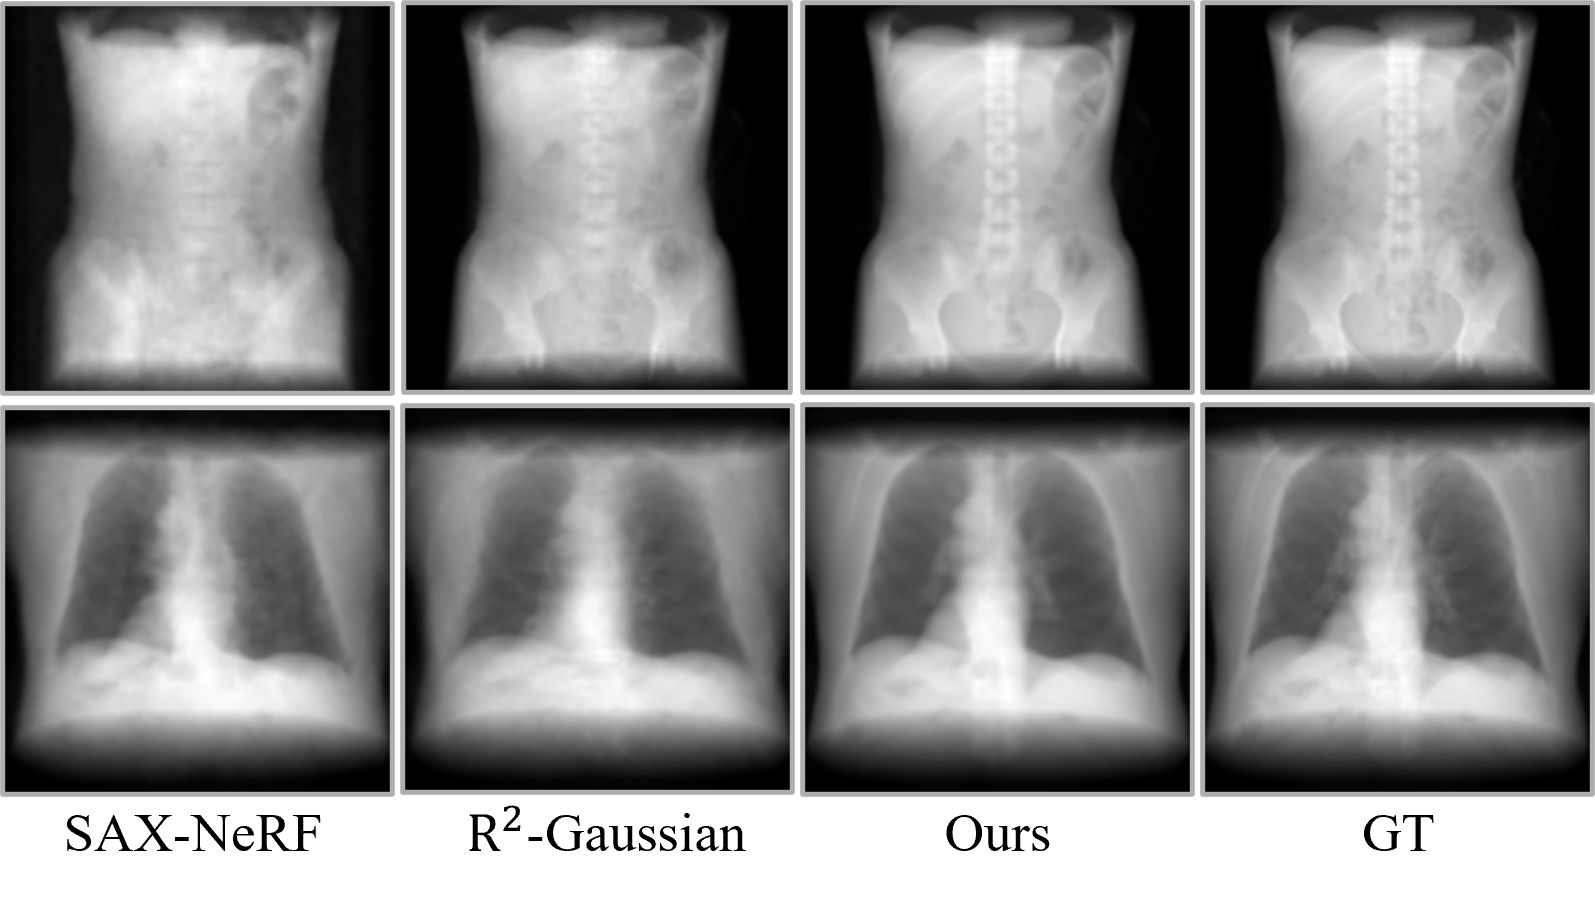

Visual comparison of CT reconstruction across different views. ILV achieves significantly cleaner structural details and consistency under both 10-view and 24-view sparse settings compared to existing methods.

Synthesis results for X-ray novel view synthesis. ILV successfully recovers sharp object boundaries and consistent internal structures.